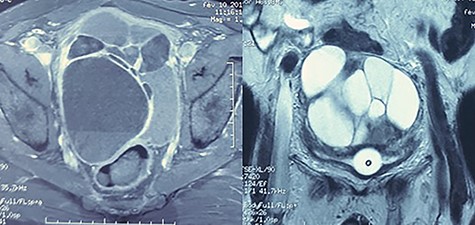

A hydatic cyst was suspected but hydatic serology was done twice and was negative. We completed in the first place by a urethrocystography on which we notice the presence of a 12-cm mass projecting on the bladder area (Fig. 2). And to better and further characterize this cystic formation, a pelvic magnetic resonance imaging (MRI) was performed, concluding the presence of a 13 × 10 cm supra-rectal and retro-vesical multilocular cystic formation of heterogeneous signal, with the presence of liquid level in some loci, having a T1 hypersignal (Fig. 3) and T2 hypo signal evoking a hematic content having a thin wall increasing after injection of gadolinium, the whole evoking either a hemorrhagic cystic retro-peritoneal mesothelioma or cystic lymphangioma.

MRI: multilocular cystic formation of heterogeneous signal, with the presence of liquid level in some loci, having a T1 hypersignal and T2 hyposignal.